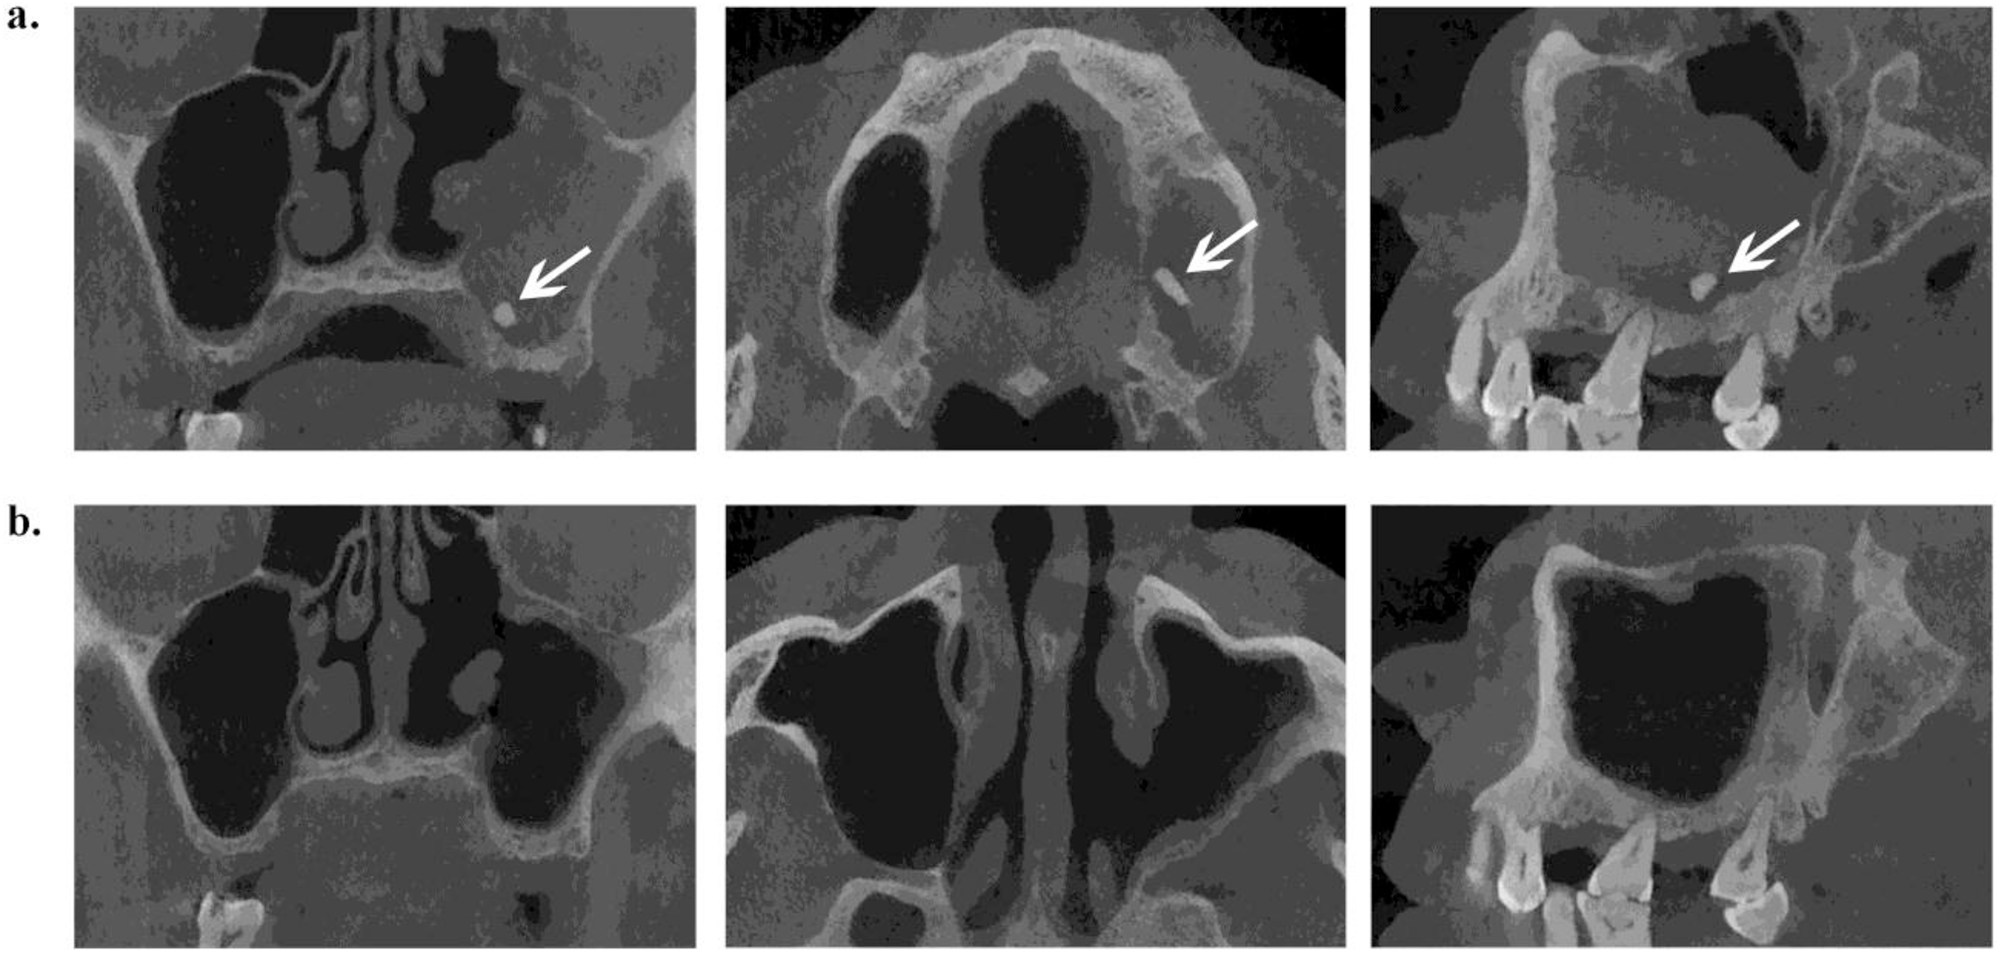

Maxillary molar root protrusion into the maxillary sinus a comparison of cone beam computed Root Of Tooth In Maxillary Sinus Radiology In each quadrant from the central to outer teeth, there are the following teeth, with the same nomenclature applying to both maxillary and mandibular teeth: Maxillary tori may appear as pathological radiopacities in the sinus but below the image of the hard palate. The root is surrounded by a periodontal ligament allowing minimal movement of the tooth within its supporting. Root Of Tooth In Maxillary Sinus Radiology.

Maxillary molar root protrusion into the maxillary sinus a comparison of cone beam computed Root Of Tooth In Maxillary Sinus Radiology This is visible radiographically as a. The root is surrounded by a periodontal ligament allowing minimal movement of the tooth within its supporting alveolar bone: This study aimed to examine the prevalence of molar roots protruding into the maxillary sinus and to determine the panoramic radiographic signs as correlated with cone beam. Roots or whole teeth accidentally displaced during an. Root Of Tooth In Maxillary Sinus Radiology.